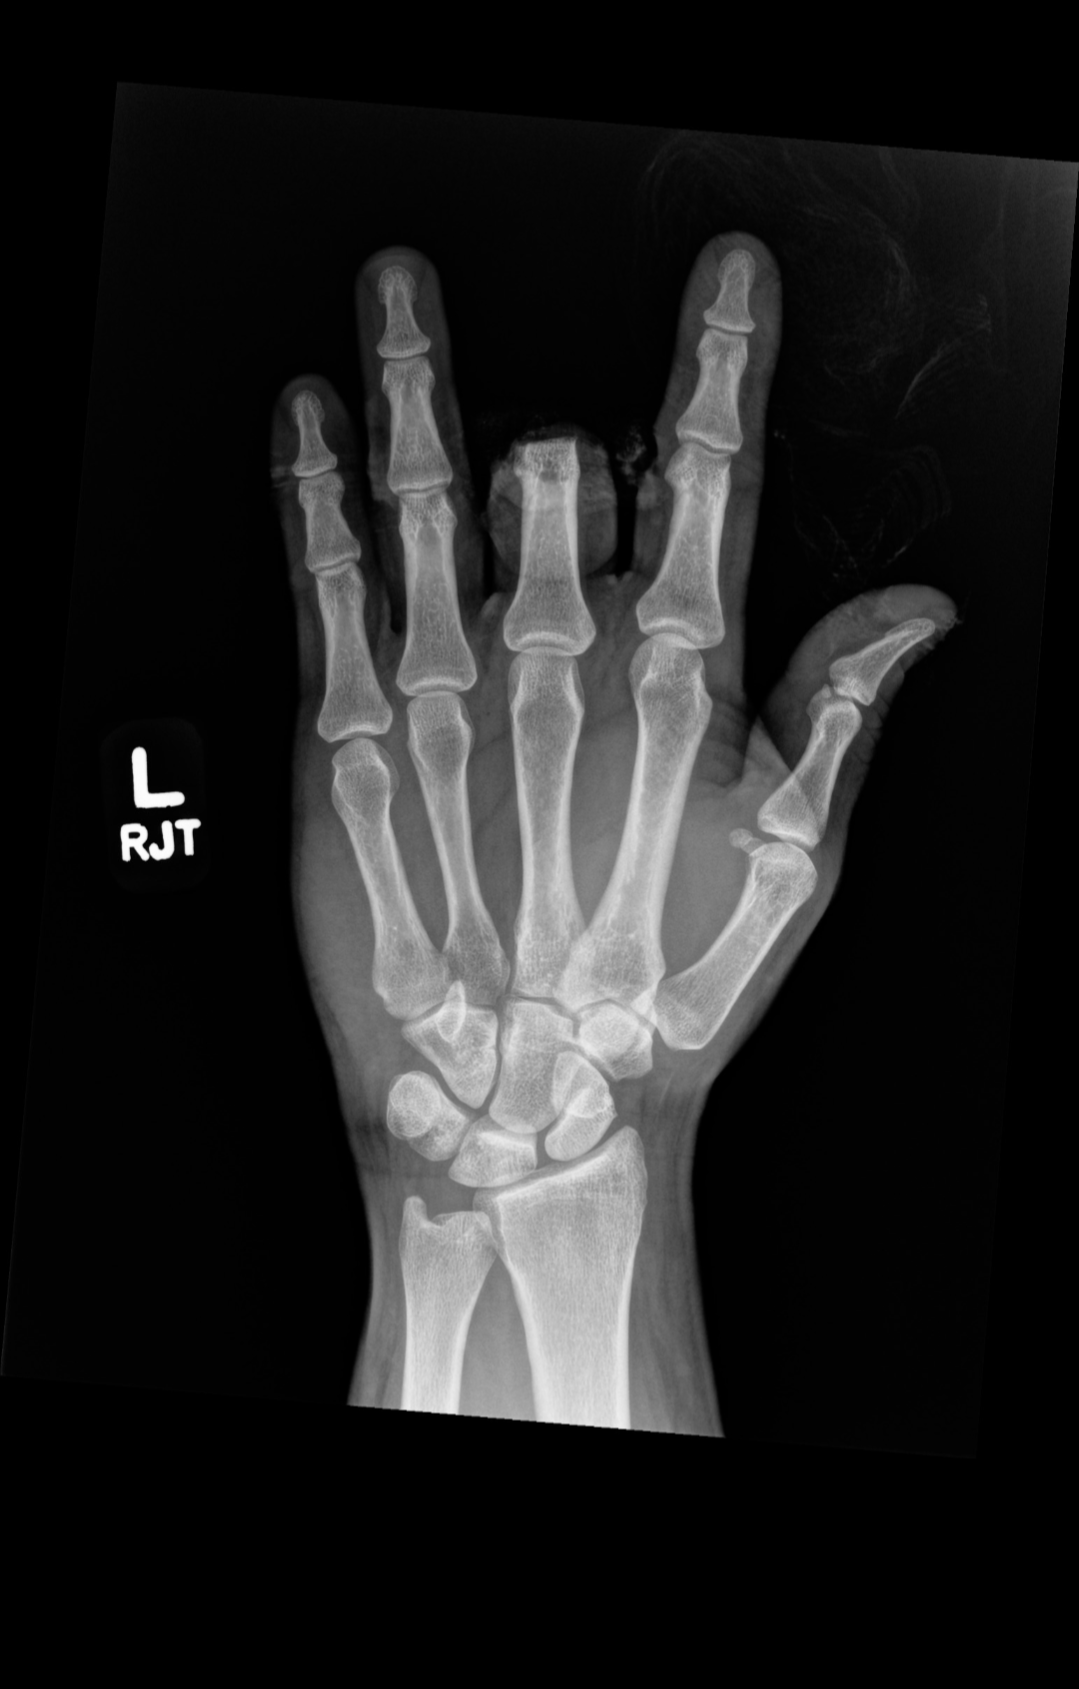

In November 2024, Colton lost his middle finger and severely injured his pointer finger in a table saw accident. He’s now facing max out-of-pocket medical costs three years in a row within just 16 months.

Colton has maintained a positive attitude despite all the recovery challenges, and now he needs help covering expenses for a prosthetic, therapy, and ongoing recovery. His pointer finger has very limited use, and he’s working hard to regain function and get back to normal life.